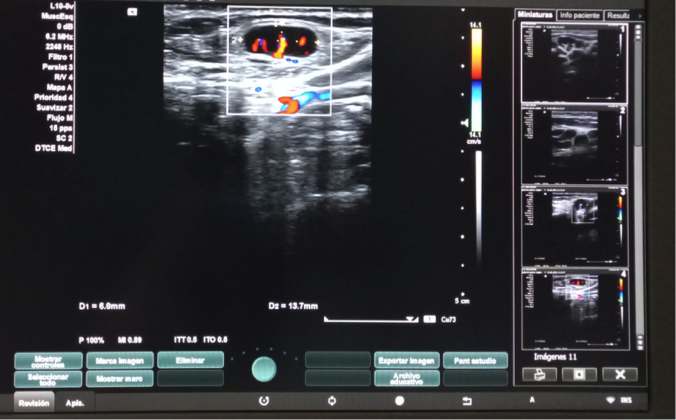

Hallazgos ecográficos

Dos adenopatías en territorio laterocervical derecho, con hilio central y doppler positivo, alguna con diámetro transversal superior al longitudinal, de probable origen reactivo y una adenopatía supraclavicular sin hilio central y con vascularización generalizada.